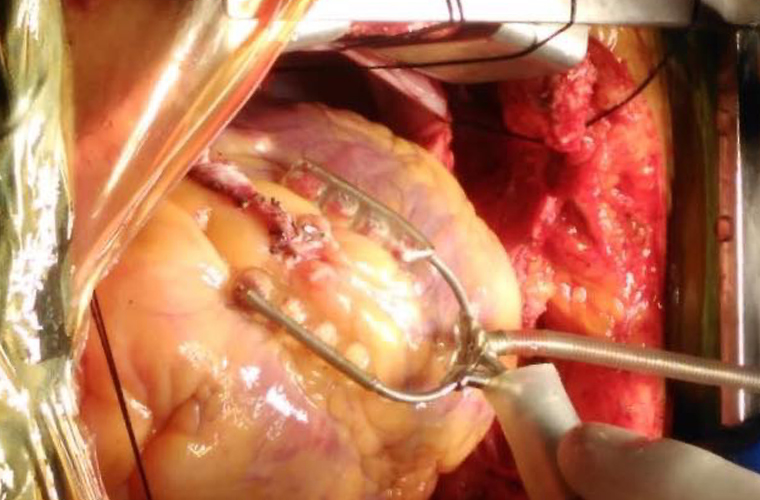

Dr.DineshShanmugaSundaram is specialized himself in each & every part of Cardiovascular & Thoracic Surgery both in Adult & Paediatric or Congenital Heart Diseases. He is both an ethical & academic surgeon,changed the trend in Cardiac Surgery to fast & safe level, as prolonged procedures in Cardiac Surgery increases postoperative complications. We aim at decreasing perioperative complications to the maximal level. Read More